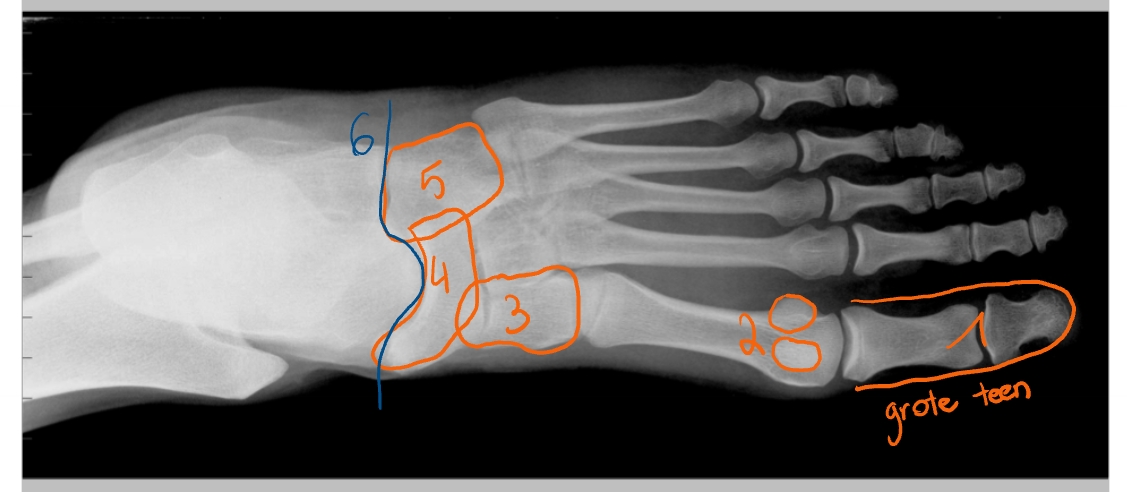

hallux

2 sesambeentjes

os cuneiforme mediale

os naviculare

os cuboideum

gewrichtslijn van Chopart

2 sesambeentjes

tuberositas van metatarsaal 5

os cuneiforme laterale

os cuboideum

os naviculare

talus

calcaneus

gewrichtslijn van Lisfranc

gewrichtslijn van Chopart